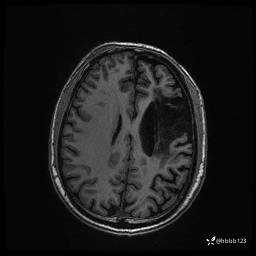

患者男,43岁。

简要病史:癫痫患者复诊,昨日发作5-6次,建议住院进一步治疗。

入院完善脑癫痫组合序列:

3d T1: